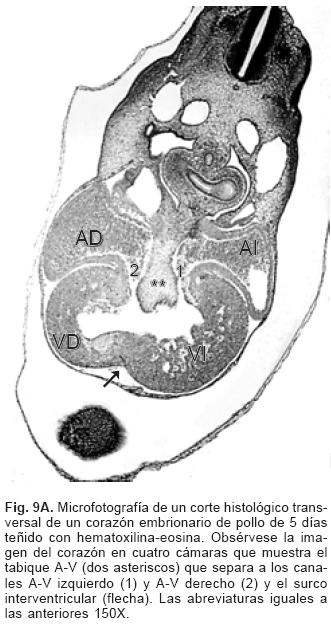

El proceso embrionario de la tabicación A–V se establece con el crecimiento y desarrollo del mesénquima cardíaco de las almohadillas endocárdicas dorsal y ventral del canal A–V que en el embrión ocurre entre los estadios (25 al 29) de Hamburguer y Hamilton17,18 (Fig. 8A), dichas almohadillas completamente desarrolladas se fusionan y conforman el tabique A–V que divide al canal A–V común en dos: derecho e izquierdo (Fig. 8B) en cuyas paredes se diferencian dos anillos fibrosos situados a desnivel, uno para la válvula tricúspide y otro para la válvula mitral (Fig. 9A). El extremo craneal de este tabique se dobla hacia la izquierda, crece dentro del canal A–V izquierdo y se transforma en el esbozo de la porción central de la valva medial (aórtica) de la válvula mitral21 (Fig. 9B), proceso que ocurre en los embriones humanos en los horizontes de Streeter del XIII al XVI.19,20 El espacio comprendido entre el tabique ventricular y la valva medial de la válvula mitral constituye el tracto de salida del ventrículo izquierdo. La valva lateral de la válvula mitral se separa como un faldón de la pared del canal A–V y del ventrículo izquierdo del que se diferencian también sus cuerdas tendinosas y músculos papilares (Fig. 9B). La válvula tricúspide se desarrolla por el mismo proceso de delaminación para conformar tres láminas de miocardio que corresponden a las valvas septal, anterior y posterior con sus respectivas cuerdas tendinosas y músculos papilares.1

La rama derecha del tabique A–V embrionario origina al tabique A–V definitivo cuyo mesénquima se transforma en músculo, el extremo anterosuperior del mismo se diferencia en el tabique membranoso del corazón (Fig. 9B).22 La porción de entrada del tabique ventricular se fusiona con la rama derecha del tabique A–V, lo que oblitera la comunicación interventricular de la porción de entrada.